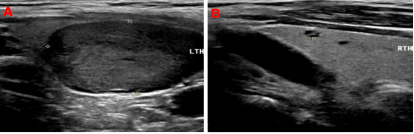

99mTc-MIBI甲状旁腺SPECT/CT融合显像图:图1+2冠状位、图3+4矢状位、图5+6横断位,提示功能亢进甲状旁腺组织(十字线交叉处)。随后的超声提示:双侧甲状旁腺区多断面超声扫查未见明显异常占位性病变;双侧甲状腺结节,其中左侧叶内一枚33mm×19mm低回声、边缘光滑、内无强回声结节。颈部B超图:A、B(纵切面)分别显示甲状腺左叶、甲状腺右叶;左叶内一低回声结节。